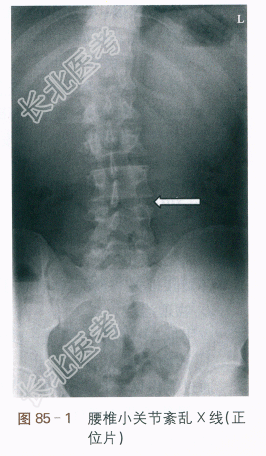

腰椎X线片提示:腰椎侧弯,腰椎轻度退变。如图85-1所示。

腰椎关节紊乱。